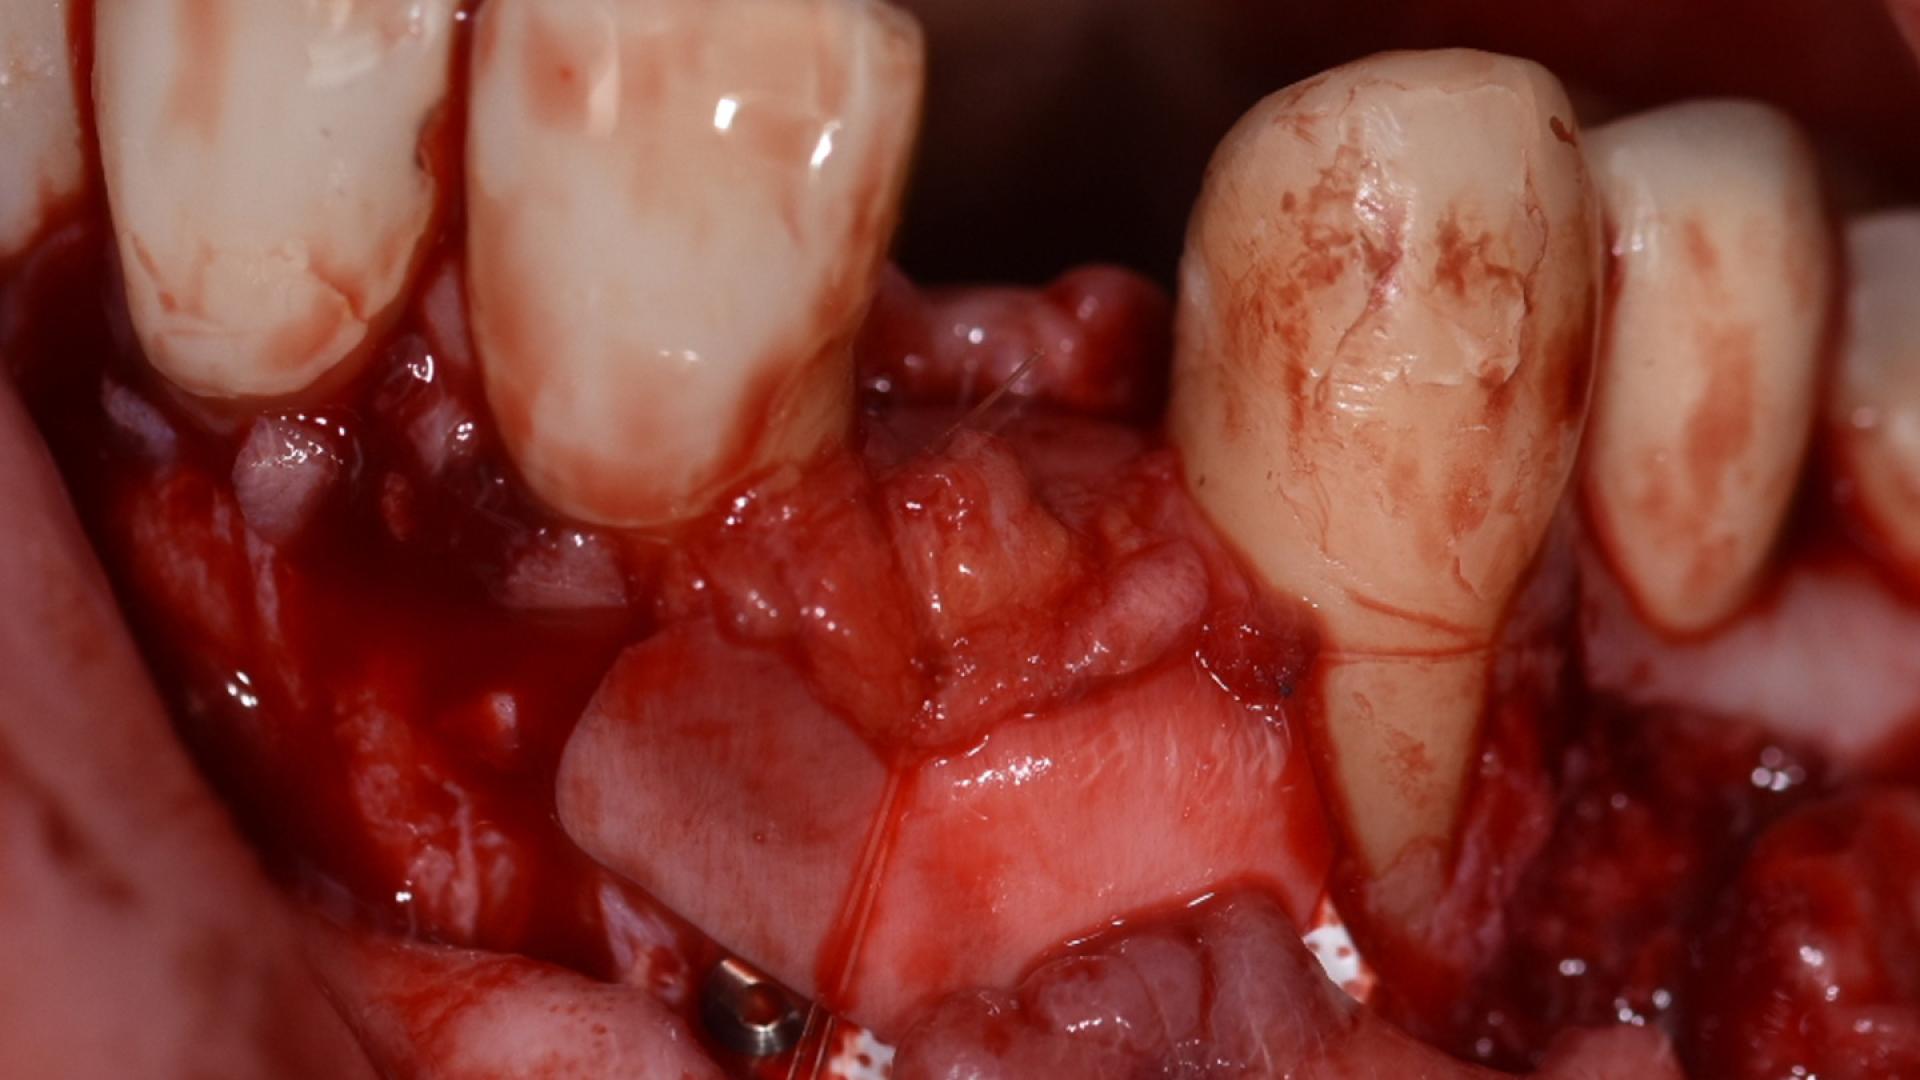

Cirugía guiada para casos complicados, implantes cortos y de gran diámetro. Solución de complicaciones.

· Introducir al alumno en las cirugías de alta complejidad en regeneración vertical y horizontal utilizando las técnicas más actuales y predecibles.

· Conocer los diferentes tipos de técnic de regeneración vertical existentes.

· Seleccionar cada técnica según el paciente, saber cuando elegirla y como evitar fallos.